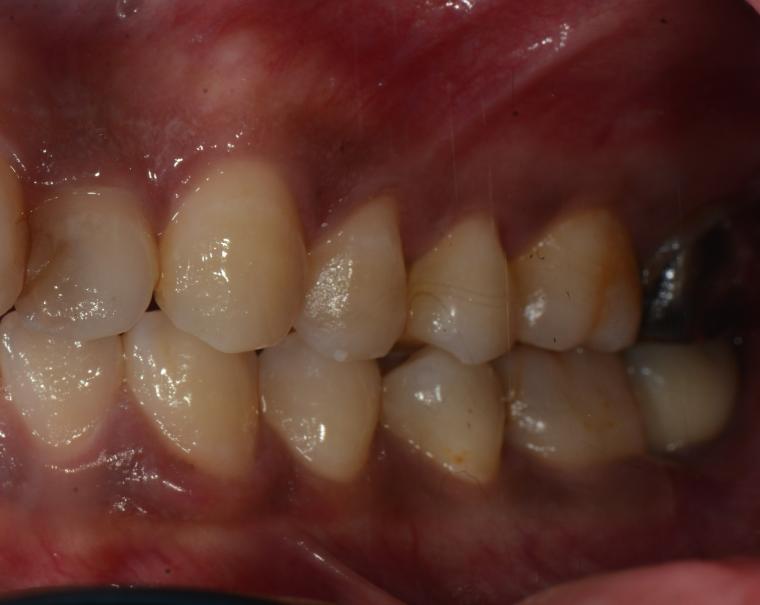

AFTER

抜歯後に土台となる骨をつくる処置の後、インプラントを埋入しました。

現在も定期検診で拝見させていただいています。